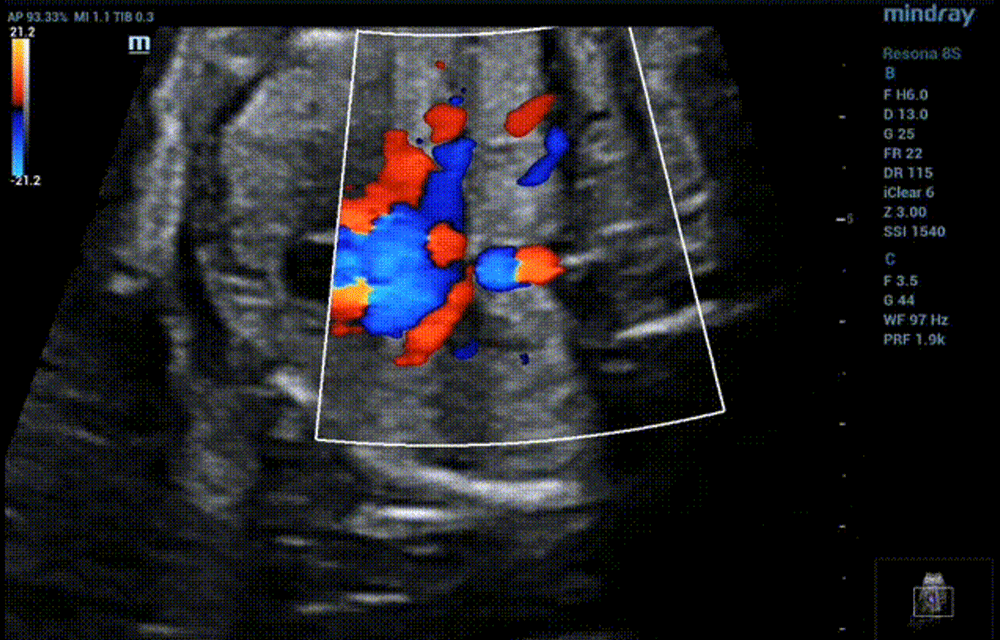

Observe pulmonary venous returning at low-level four-chamber view

• Low-level four chamber view shows LSPV and LIPV return to the coronary sinus that makes the posterior wall of the coronary sinus protruded and inner diameter broadened.

• Color Doppler shows the blood from LSPV and LIPV flowed through the coronary sinus and directly flowed into the right atrium, which crossed the right superior and right inferior pulmonary veins in a dislocation rather than confluence.

• Four chambers view of color doppler seems to show that all pulmonary veins return to the left atrium. Actually, LSPV and LIPV only brush below the LV rather than drain into the left atrium.